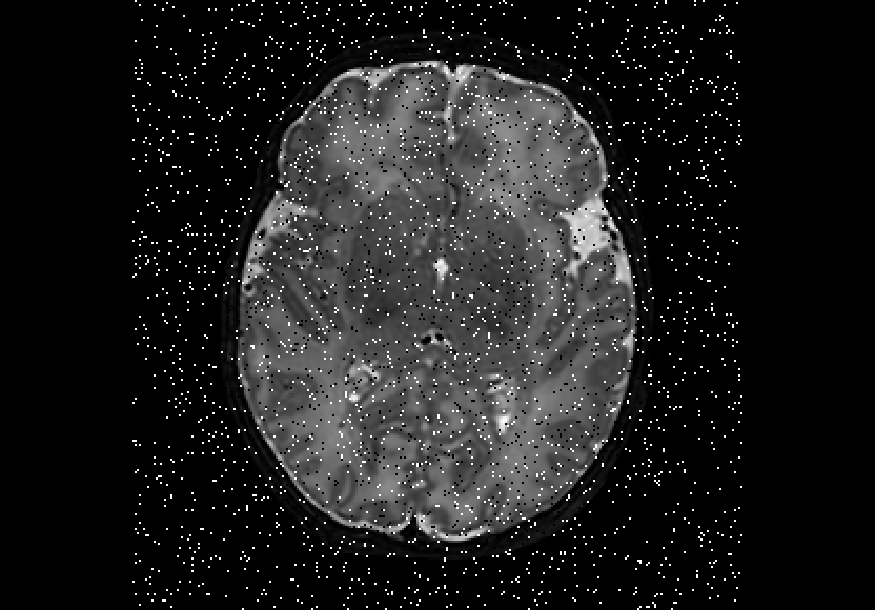

We also explored impulse noise corruptions, such as those introduced by noisy communications channels, faulty memory locations, or damage in channel decoders [6]. The impulse noise generating filter we used in this study is based on the salt-and-pepper (SNP) technique, which randomly generates black and white pixels on the image of interest. The function we used takes into account a parameter called prob, where 0 prob 0.5. A random number is generated for each pixel; if it is less than prob then the function paints the pixel with black, if it is greater than 1-prob then it paints the pixel with white, otherwise the pixel is left unchanged. In other words, the higher the value of prob, the noisier the output can become. We used different values for prob, in particular prob ={0.01, 0.03, 0.05, 0.07, 0.10, 0.15, 0.20}, to create seven different noisy datasets named snp_prob. Examples of axial slices are shown in Figure 4.